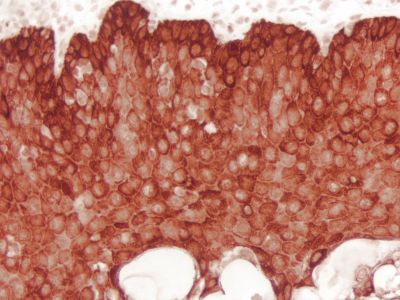

The ImmPRESS Polymer Reagents produce outstanding immunohistochemistry and immunocytochemistry results due to increased target accessibility, binding specificity, and signal intensity along with low background staining.

Staining Procedure

The staining procedure is simple as shown in the diagram below. Following a blocking step with the diluted normal horse serum, sections are incubated with primary antibody. After a brief wash, the appropriate ImmPRESS Reagent is added to the sections and incubated for 30 minutes. Sections are again rinsed and the slides are developed with the peroxidase substrate of choice.